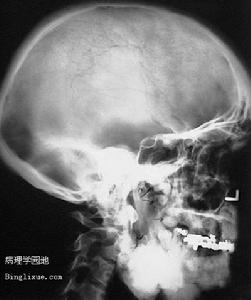

(1)骨瘤:本症的骨瘤大多數是良性的,從輕微的皮質增厚到大量的骨質增生不等,甚至可見有莖性的巨大骨瘤,多發生在顱骨、上領骨及下頜骨,四肢長骨亦有發生。並有牙齒畸形,如過剩齒、阻生齒、牙源性囊腫、牙源性腫瘤等。Fader將牙齒畸形稱為本症的第4特症。骨瘤及牙齒形成異常往往先於大腸息肉。

GARDNER綜合症2、X線檢查:凡懷疑有骨瘤或骨質異常增生者應攝正側位片,以了解有無皮質增厚或骨質增生。胃腸鋇餐造影和鋇劑灌腸雙重對比造影,均有助於發現消化道內的可疑息肉。